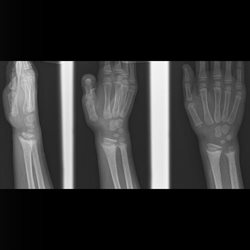

Pediatric Extremities 3

Pediatric arm, elbow and wrist cases